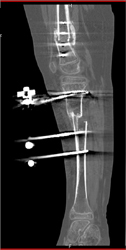

Congenital Hip Dysplasia With Open Reduction Internal Fixation (ORIF)